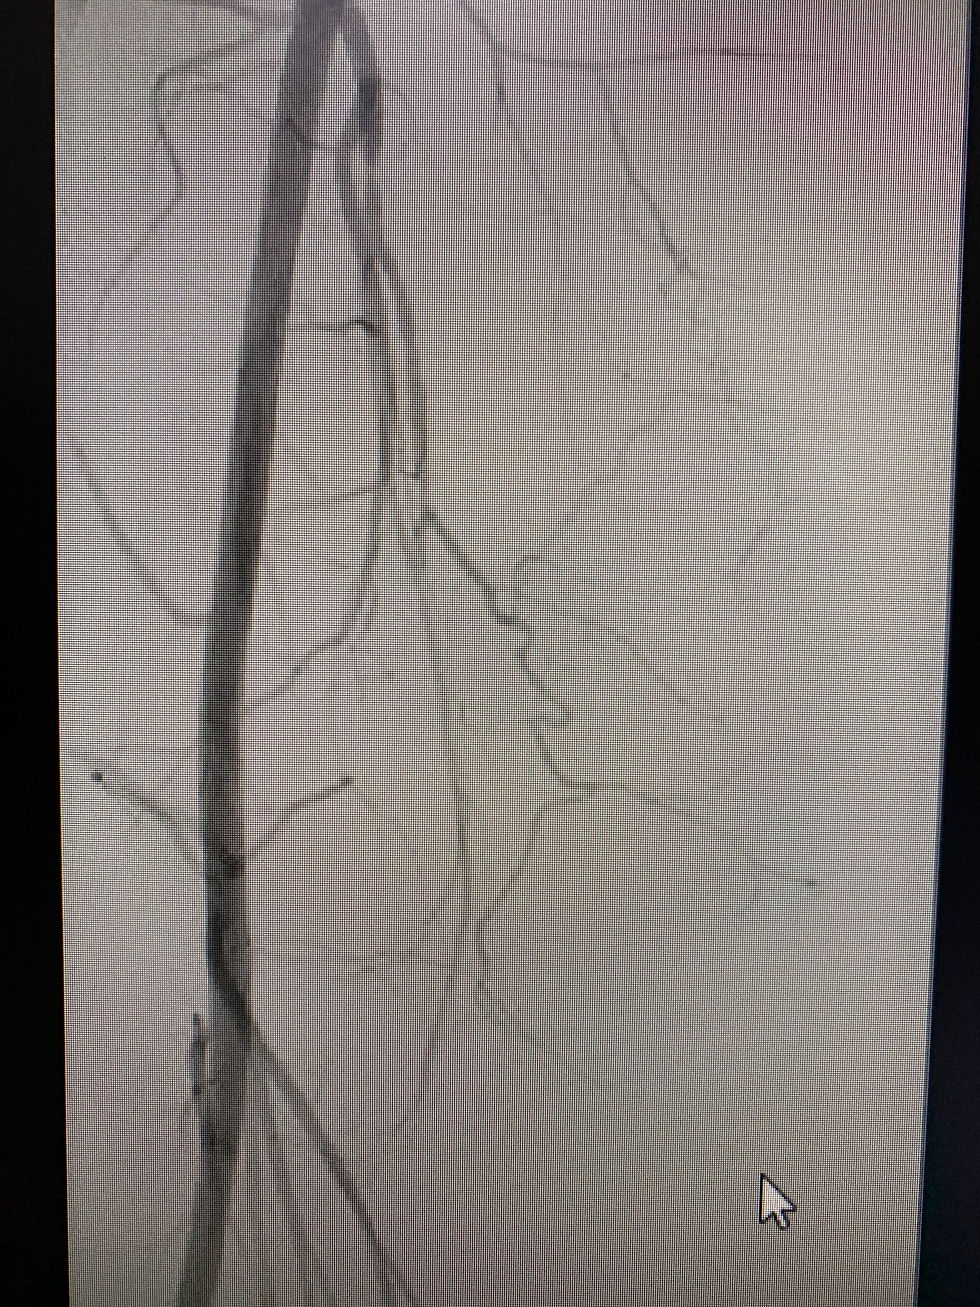

Angioplastia periférica